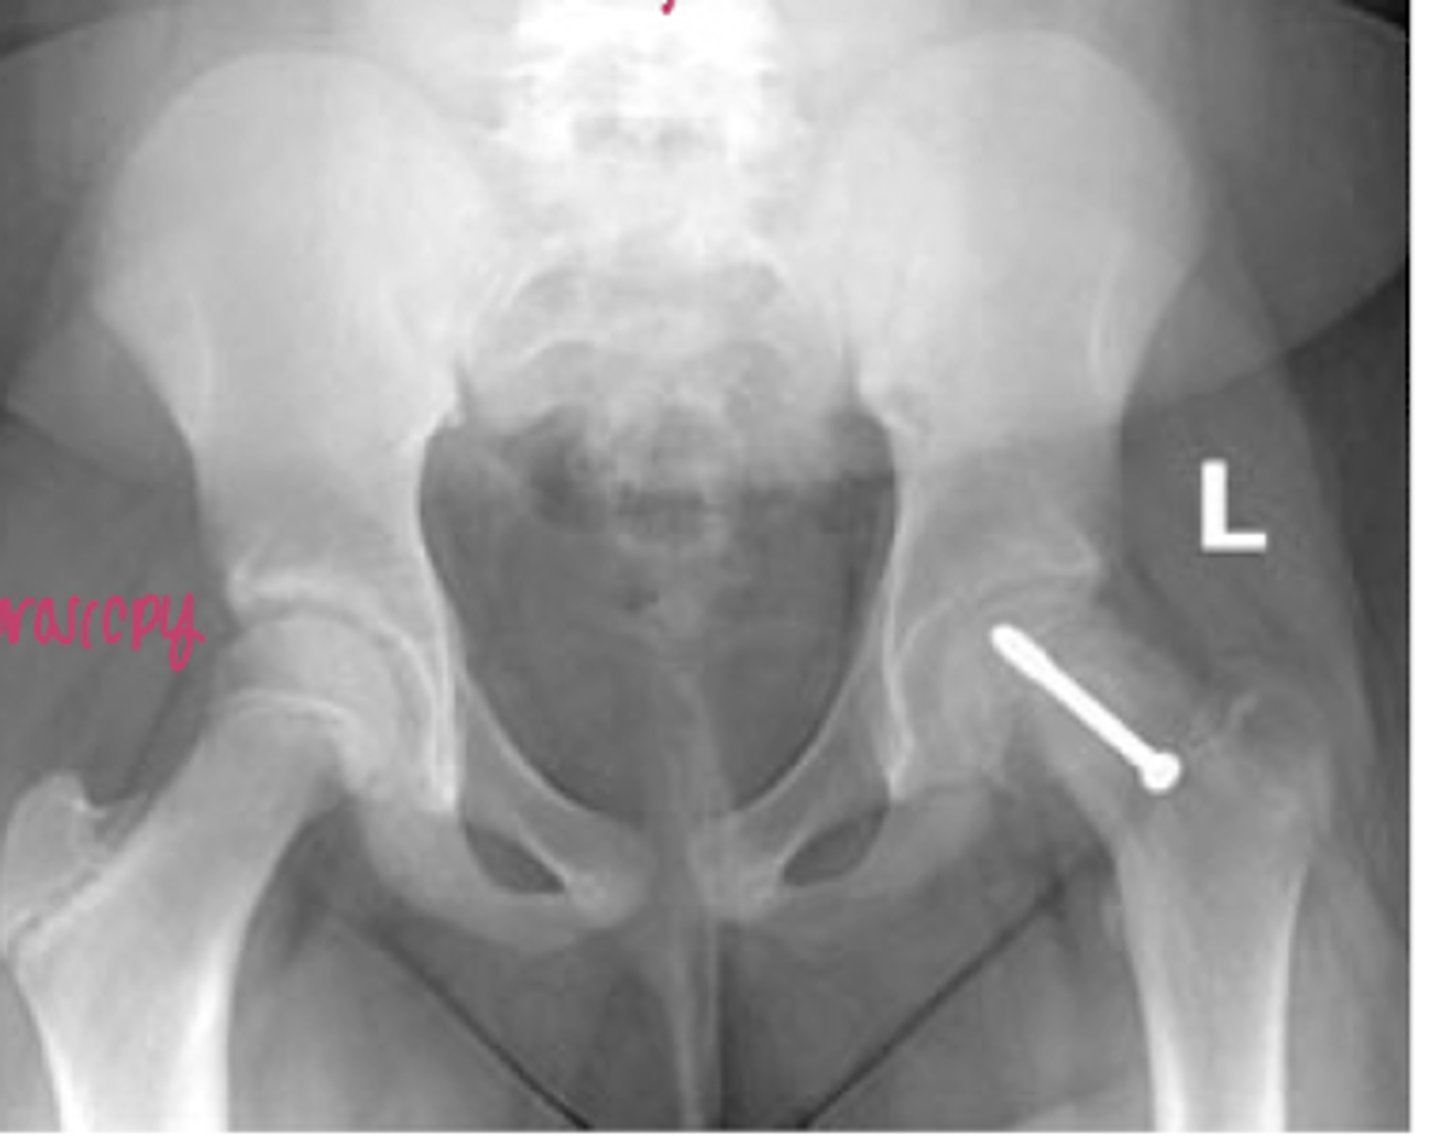

hip dysplasia on the Left photo

the L hip is worse than the R hip

very acute center edge angle

periacetabular osteotomy

used for hip dysplasia. break femur and pelvis, rotate them to provide greater joint angle